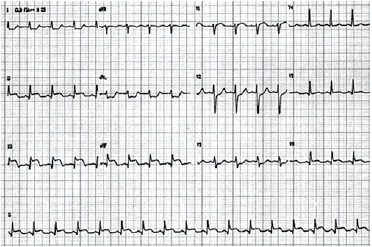

Homem de 68 anos é internado com a hipótese de uma síndrome coronariana aguda. Exame físico à chegada (cerca de 1 hora do início do quadro): pressão arterial: 100 x 60 mmHg; ausculta pulmonar: crepitações nas bases pulmonares. Eletrocardiograma realizado é mostrado a seguir.

Neste momento, é correto afirmar: